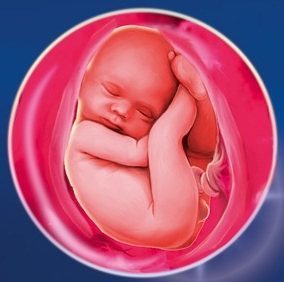

Плід на 39 тижні вагітності

Дитина зараз дуже активно запасається підшкірним жиром, що робить його шкіру гладкою і світлою. Розмір і вага плоду на 39 тижні вагітності становить 48 см і 3,2 кг відповідно. Варто відзначити, що ці дані можуть змінюватися, в залежності від спадкових факторів.

Зараз плід вже розвинений і готовий до самостійного життя. Тепер всі органи можуть функціонувати, а його легені здатні розкритися для першого подиху. Навіть травна система вже готова до того, щоб переробляти їжу. Таким чином, вже зараз по його кишечнику проходить меконій, який є первородним калом. Шлуночок, хоч і маленький, але виробляє пепсин, а підшлункова залоза готова стати помічником в травленні. Зараз там немає абсолютно ніяких бактерій. Вони з'являться тільки з першим годуванням дитинку молоком матері.

На цьому етапі плід активно розвиває свій смоктальний апарат. Поки жувальні рефлекси і слинні залози погано розвинені, але вже після перших годувань ці процеси налагодяться.

Середня довжина плоду становить приблизно 50 см, а вага 3 кг - 3 кг 500 г. Шкіра має блідо-рожевий колір, добре розвинена підшкірна основа, Пушкова волосся майже немає, довжина волосся на голові приблизно 2 см. Очі можуть фокусуватися на відстані 20 - 30 см (відстань до особи мами в період годування). Є чутливість по контрастності і гостроті, рефракція і акомодація, наявність об'ємного, біполярного, кольорового зору, плід реагує на мелькання і рух.

Зростання плоду - близько 50 см, вага може варіюватися від 3 до 3,5 кг. Шкіра поступово набуває остаточного, блідо-рожевий колір, розвинулася підшкірна клітковина, пушок на шкірі практично зник, волосся на голові можуть досягати 2 см.

Відстань, на якому здатні фокусуватися очі малюка - 20-30 сантиметрів. Це якраз те відстань, що відокремлює малюка від імені матері в процесі грудного годування. Очі розвинені настільки, що присутній аккомодация, рефракція, чутливість по гостроті зору і контрастності, об'ємний зір, а також кольорове і біполярний. Малюк вже здатний реагувати на мельтешение предмета і на його рух, здатний визначити глибину і дистанцію.